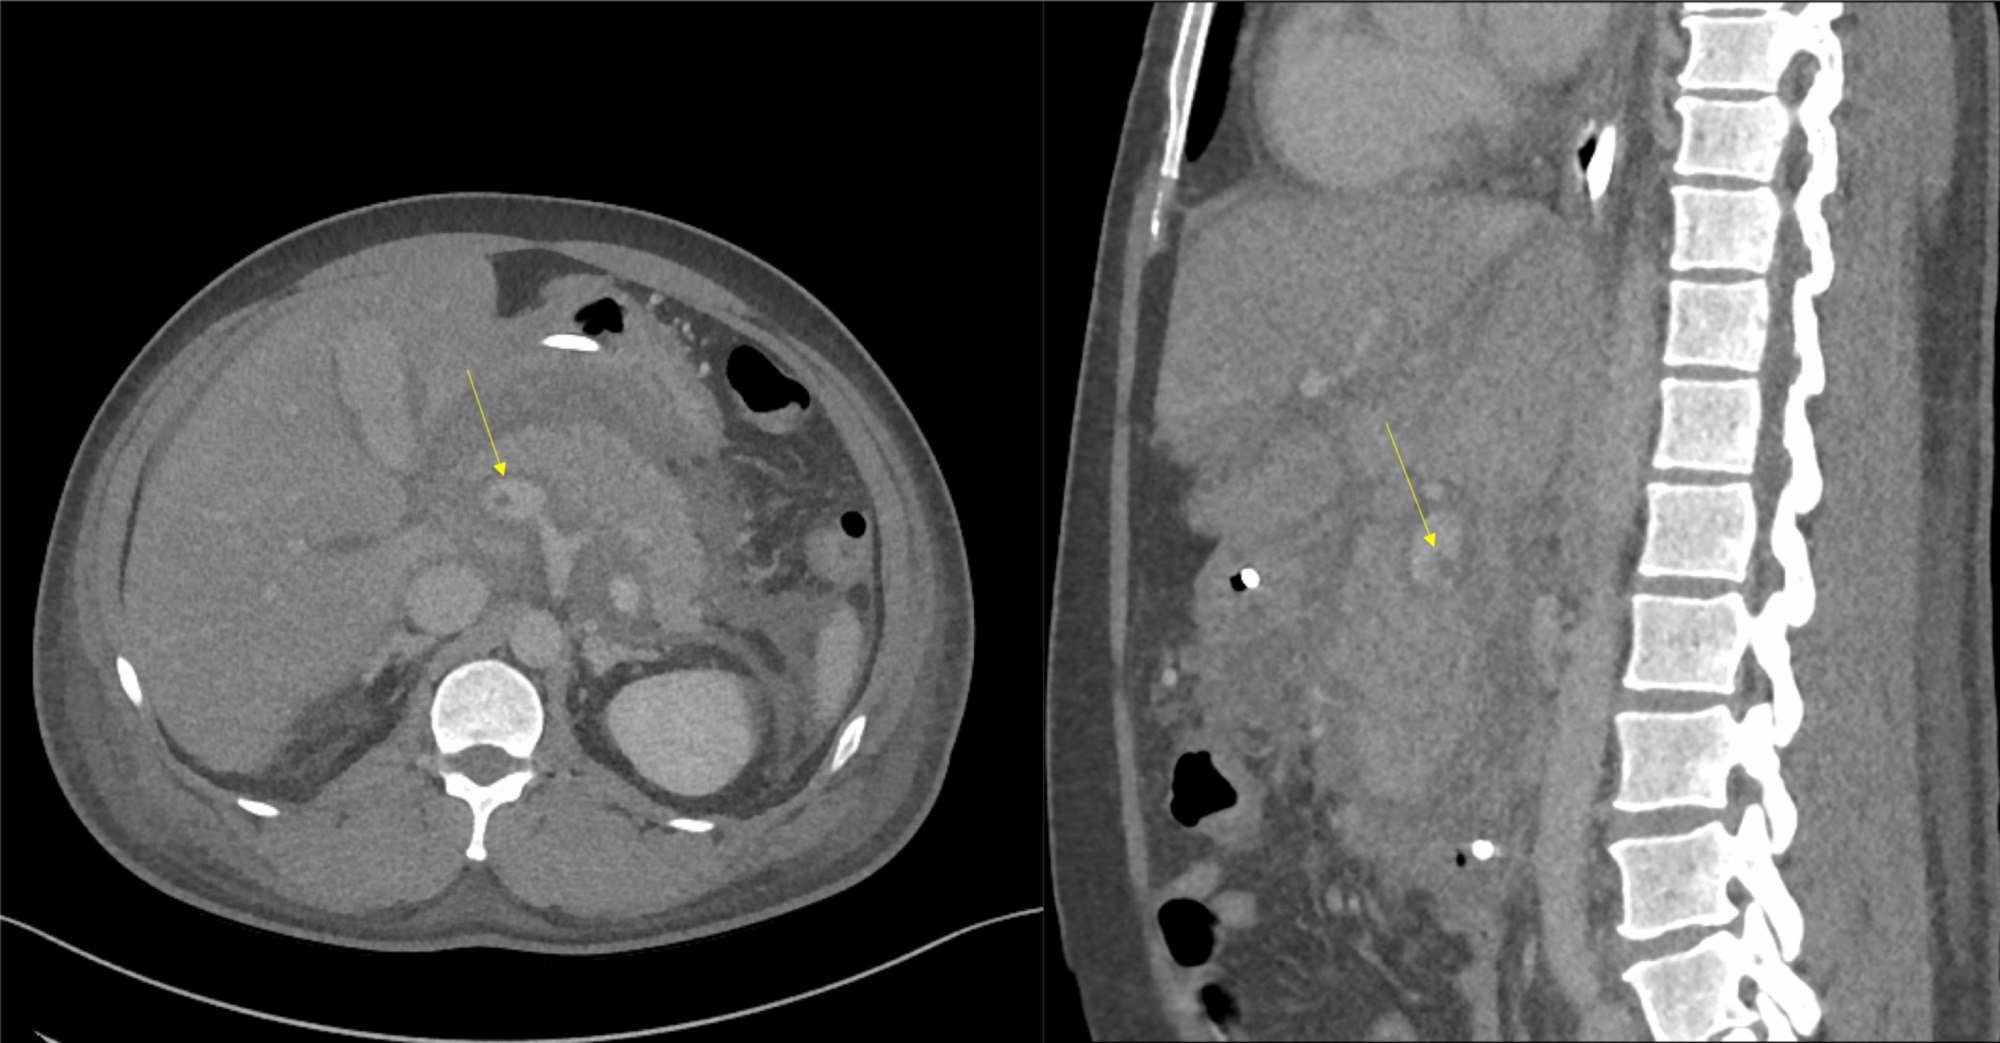

After five days, feeding through a Dobhoff tube was initiated. Despite the improvements in abdominal tenderness and triglyceride levels, one episode of fever (38.5 °C) was observed. A repeat CT scan of the abdomen with contrast revealed partial PVT (Figure 3), and enoxaparin was initiated.